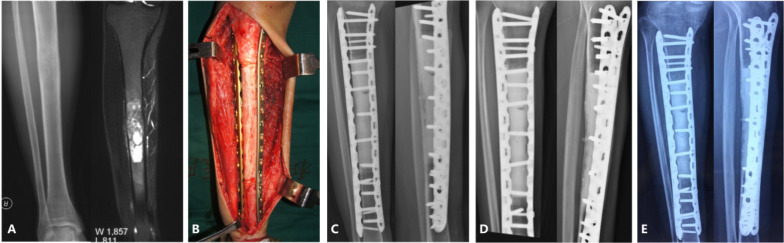

Methods: A retrospective study was conducted on 144 patients who underwent intercalary biological reconstruction for primary malignant bone tumors at a single institution between January 2012 and July 2023. Seventy-two patients underwent intercalary liquid nitrogen-frozen autograft reconstruction, and 72 patients underwent intercalary allograft reconstruction in this study. A modified International Society of Limb Salvage classification system was used to evaluate the complications.

Results: The mean follow-up time was 60.2 ± 32.1 (range, 12-149) months. The mean union time was 9.6 months in the frozen autograft group and 15.9 months in the allograft group (p < 0.001). The 5-year overall survivorship was 86.8% in the frozen autograft group and 73.2% in the allograft group (p = 0.017). The average MSTS-93 score was comparable between the two groups (89.7% by autograft versus 87.6% by allograft, p > 0.05). Of the patients, 48.6% (70/144) had at least one complication. The most common complications were bone nonunion (20.8%, 30/144), followed by structural failure (17.4%, 25/144), tumor progression (10.4%, 15/144), infection (10.4%, 15/144), and soft tissue failures (5.6%, 8/144). Higher rates of bone nonunion (type 4B; p = 0.002) and structural failure (type 3B; p = 0.004) were obtained in the allograft group than in the frozen autograft group.

Conclusions: The intercalary frozen autografts had shorter union time and lower complication rates than allograft reconstruction. Therefore, we recommend that frozen autograft reconstruction be considered when the tumor bone has not suffered severe osteolytic injury or pathological fracture.